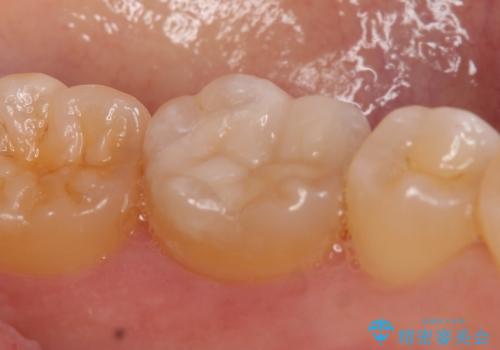

セラミックインレー しみる奥歯の治療

- 左下の奥歯がしみるので診て欲しいといらっしゃった方の症例です。

左下6の古い銀歯及び虫歯を除去し、セラミックインレーによる修復を行いました。